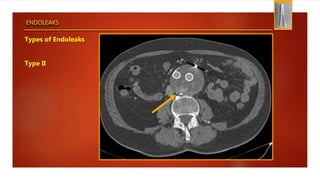

Types of Endoleaks

Type II

ENDOLEAKS